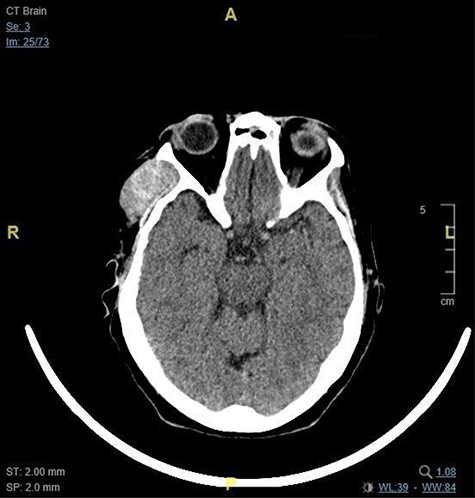

On examination, the patient had a 4-cm non-tender slightly fluctuant non-pulsatile mass over the right temporal area, clinically suggestive of a lipoma. On examination, there were no melanocytic naevi on the overlying and surrounding skin, and fundoscopy was normal. Blood investigations were within normal limits, except for thyroid function tests, which were suggestive of hypothyroidism. Computed tomography (CT) imaging of the head, neck and thorax demonstrated a 2 × 4 x 4 cm well-defined subcutaneous enhancing soft tissue formation in the right temporal fossa (Fig. 1). There was no cervical lymphadenopathy and no lung consolidation or suspicious lung nodules.

This image shows the 2 x 4 x 4 cm right temporal fossa lesion as seen on CT brain in the axial plane.